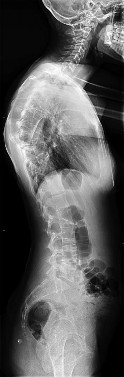

A 15-year-old female gymnast presents with persistent lower back pain. Lateral radiographs of the lumbar spine reveal a pars interarticularis defect at L5 and a forward translation of L5 on S1. The superior endplate of S1 is divided into four equal parts, and the posterior cortex of L5 sits over the second quartile. According to the Meyerding classification, what is the grade of this spondylolisthesis?